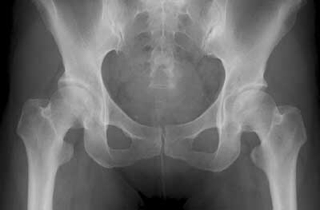

[レントゲンで分かる今までの軌跡!]

参考:正常な股関節